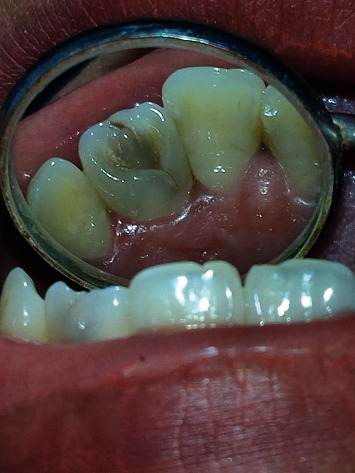

形态发育异常在上颌侧切牙中很常见,但在一颗牙齿中同时出现两种发育异常的情况却相对少见。在本病例报告中,我们介绍了一例在左侧切牙中同时出现爪状尖牙和内陷牙的病例。此类病例的早期诊断和及时治疗对于防止任何不良后果的发生非常重要。

Morphogenic developmental anomalies are common in maxillary lateral incisors, but simultaneous occurrence of two developmental anomalies in a single tooth is relatively uncommon. In this case report, we present a case of cooccurrence of the talon's cusp with dens invaginatus in the left lateral incisor tooth. Early diagnosis and prompt treatment of such cases are important to prevent any untoward consequences.